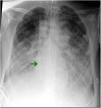

Sin embargo, toda técnica tiene sus posibles complicaciones. En el caso de las cánulas bicava, el 10% presenta migración o mal posicionamiento tras la inserción, por lo que la zona distal podría avanzar hacia las cámaras cardiacas, con riesgo de perforación, o incluso parecer que está normoposicionada por fluoroscopia (en vena cava inferior) y encontrarse alojada en venas suprahepáticas, como mostramos en el ejemplo (fig. 2 y en el vídeo del anexo A). Esta complicación da lugar a una disminución de los flujos de drenaje por incapacidad de succión del territorio inferior y, como consecuencia, origina una inadecuada oxigenación del paciente, por lo que cada vez se recomienda más la fluoroscopia asociada al control ecográfico para confirmar la normoposición de la cánula de ECMO y la posterior monitorización en la unidad de cuidados intensivos4.